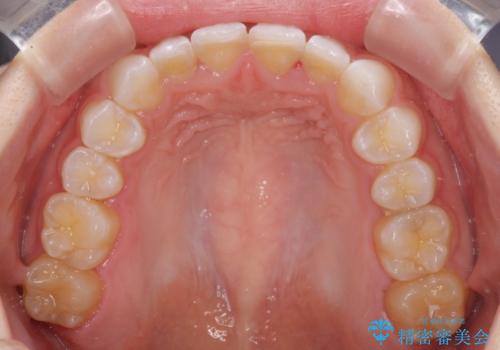

デコボコと深い咬み合わせの改善 インビザラインによる矯正治療

- 口元のデコボコと深い咬み合わせ(ディープバイト)を気にして来院された患者様です。

インビザラインによる上下歯列の拡大と、IPR(歯と歯の間を削る)にるスペースの獲得により、口元のデコボコとディープバイトを改善することとしました。

インビザラインは、装着していない時間がどれだけ短いかが、治療期間を大きく左右します。こちらの患者様は1日22時間以上、毎日欠かさず装着してくださったため、1年強という短期間で満足のいく歯列に整えることができました。